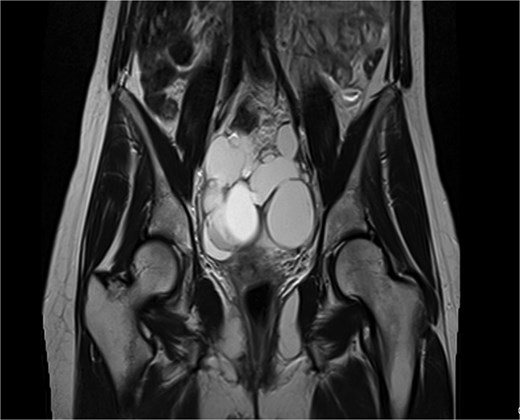

Pelvic ultrasound showed a large multicystic lesion occupying most of the pelvic cavity and pressing on nearby organs. Magnetic resonance imaging (MRI) provided a clearer picture, revealing a multilocular cystic mass displacing the uterus, ovaries, and rectosigmoid colon (Figs 1 and 2). Some cystic areas contained clear fluid, while others showed haemorrhagic or proteinaceous content, raising suspicion of a mucinous cystadenoma or borderline ovarian tumor.

Coronal T2-weighted pelvic MRI showing a large multilocular cystic lesion occupying the pelvic cavity and displacing adjacent organs.